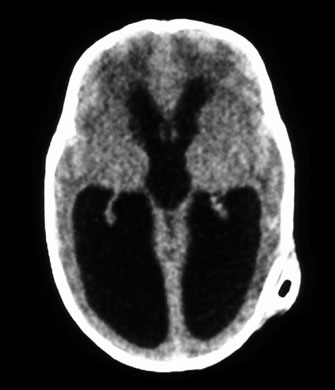

Prognosis for recovery depends on etiology, age of onset, and severity of brain damage (Fig. 7). Although such children often remain visually handicapped, dramatic recovery may ensue occasionally.36 Cortical visual loss from perinatal hypoxia/ischemia has a particularly poor prognosis if congenital, but up to a 70% recovery rate if acquired.37 Although hydrocephalus, brain dysgenesis, and infections may produce cortical visual loss, by far the most common cause of CVI in the developed world is perinatal hypoxia. In term infants, damage primarily affects the watershed areas of the cerebral cortex (frontal and parieto-occipital regions). In premature babies, however, the damage is predominantly periventricular. Age-related differences in the developing intracranial vascular systems may account for the disparate sites of injury. The watershed zone in term infants (and adults) is at the parieto-occipital junction, whereas in preterm infants it is in the subcortical area.38

Fig. 7. Computed tomography of child with cortical visual impairment resulting from congenital hydrocephalus. Note significant ex vacuo dilatation of the ventricles posteriorly, with shunt catheter in place.